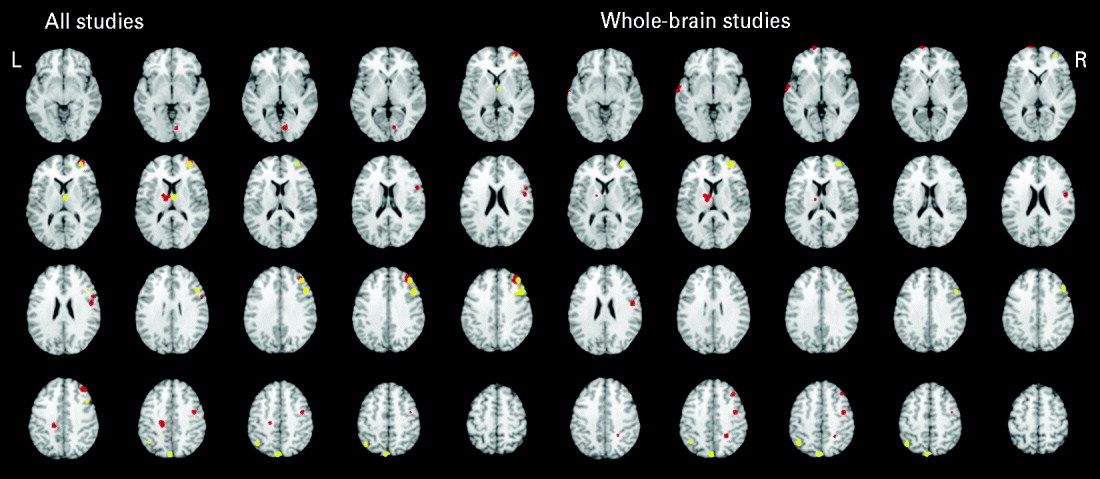

Table 3 and Fig. 2 present the significant functional activations from the 17 studies (18 samples of relatives and controls). Eight clusters were found for the controls greater than relatives contrast and six clusters were found in the relatives greater than controls contrast. In both of the contrasts, two overlapping right middle frontal regions consistently showed hypo- and hyperactivity in relatives. Table 2 provides a qualitative review of prefrontal activation patterns in individual studies and is elaborated on in the discussion to better understand the current results. Additionally, control subjects activated to a greater degree the right inferior frontal, right precentral, left posterior cingulate, left thalamus and right lingual regions compared to relatives. By contrast, relatives activated to a greater degree the right superior frontal, right thalamus, right precentral, left inferior parietal and left precuneus regions compared to controls.

Fig. 2. Above-threshold brain activations for contrasts of controls greater than relatives (red) and relatives greater than controls (yellow) for all executive functioning studies combined and whole-brain studies only. L, left; R, right.

A separate analysis of seven whole-brain studies (eight samples) was conducted to assess the potential impact of a prior hypothesis testing used in ROI and hybrid whole-brain/ROI approaches on the meta-analysis results (Table 3, Fig. 2). Eight clusters were found for the controls greater than relatives contrast and four clusters were found for the relatives greater than controls contrast. Many commonalities were found between the two analyses. Notable differences from the all-studies analysis included the finding that the middle frontal regions solely demonstrated hyperactivity in relatives compared to controls, suggesting that inclusion of ROI and hybrid approaches biased towards finding functional activations in the middle frontal region and specifically reduced activation.